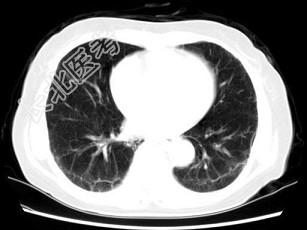

- 单项选择题女,35岁, 咳嗽,咳痰, 发热3月余,胸部CT如图, 最可能的诊断为 ( )

A、类风湿肺炎

B、红斑狼疮性肺炎

C、间质性肺炎

D、肺结节病

E、肺部感染